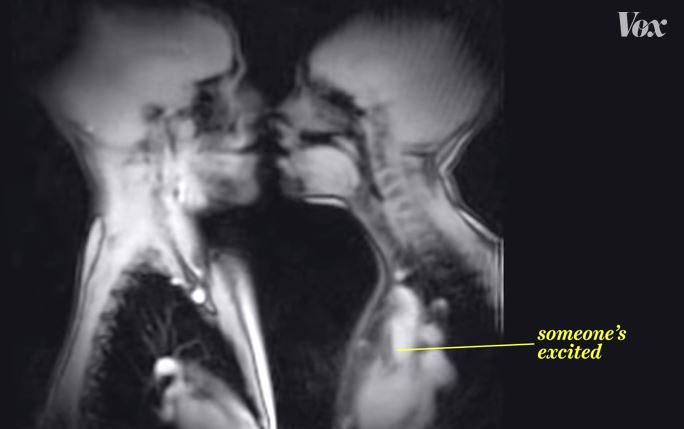

Cosa succede realmente al tuo corpo quando fai l’amore? Un video realizzato attraverso una risonanza magnetica tomografica mostra una scena di sesso da un punto di vista strettamente tecnico.

Si intitola: “La vita sembra davvero diversa attraverso una macchina per risonanza magnetica” ed è stato visualizzato più di 15 milioni di volte. Non viene mostrato solo l’atto sessuale, ma anche gli altri effetti dell’eccitamento sul fisico.

Si parte dal bacio con la lingua, si prosegue con l’atto di penetrazione vero e proprio, per poi arrivare a quello della fecondazione, quando il bambino è stato ormai concepito e si trova all’interno del grembo materno. Davvero emozionante.